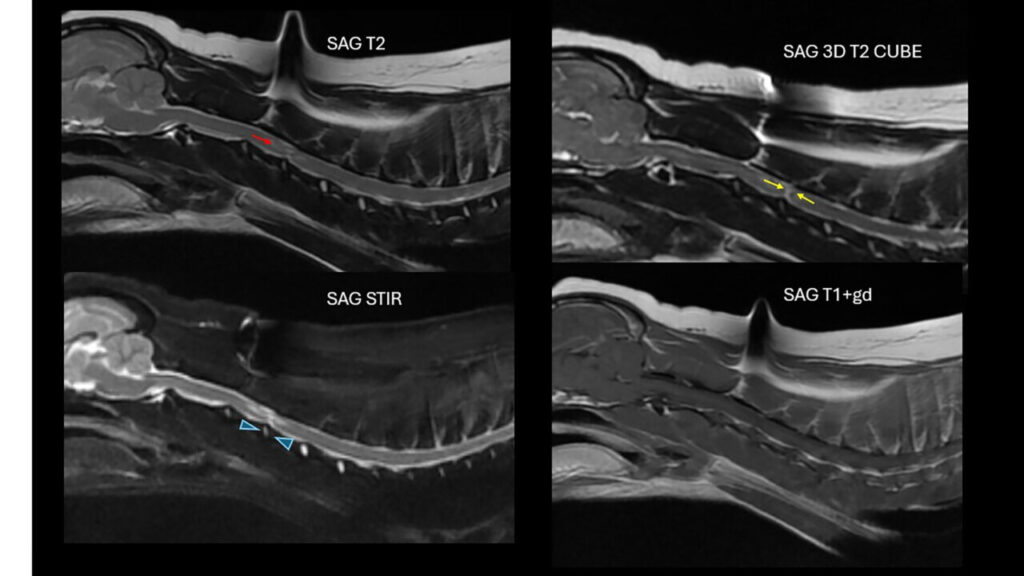

Se hospitalizó para realizar el protocolo diagnóstico con RM de los segmentos medulares comprendidos entre C1-T2. El estudio mediante RM (1,5 T) de la columna cervical se realizó incluyendo las siguientes secuencias: sagitales (T2w, 3D T2, STIR, T1w, T1w+Gd); transversales (T1w, T2w, T1w+Gd); dorsales (FIESTA, 3D). Se observó una pérdida de volumen del disco C3-C4 que mantenía una señal correcta en T2w. Justo dorsal al disco y, a nivel intramedular, se apreció una marcada lesión lineal hiperintensa en T2w y STIR e hipointensa en T1w que atravesaba la médula espinal en sentido dorsoventral, ligeramente lateralizada a la derecha. Tanto craneal como caudal a dicha lesión, hasta la mitad caudal de C3 y a la mitad craneal de C4, se vio una señal intramedular, hiperintensa en T2w y STIR, pero más difusa, también lateralizada a la derecha y dorsal. Este estudio no mostró evidencia de material extradural que causara compresión medular (imágenes 3A y 3B).

Imagen 3. Caso 2. A) RM, cortes sagitales utilizando distintos tipos de secuencias. Se aprecia un trayecto en dirección dorsal desde el espacio IV C3-C4 hasta el parénquima medular (flechas amarillas; sag 3D T2 cube) que muestra señal hiperintensa craneal y caudalmente a dicho espacio (flecha roja; sag T2). El disco C3-C4 muestra un menor volumen (puntas de flecha azules; sag STIR) y no se evidencia la presencia de material degenerado compresivo en el canal vertebral (sag T1+gd). Resonancia magnética informada por ProtonVet. B) RM, cortes transversales en T2 y T1 poscontraste. Se observan las zonas de hiperintensidad en T2 craneal y caudalmente (flechas amarillas) al trayecto que va en dirección ventro-dorsal (puntas de flecha rojas) que podrían ser compatibles con zonas de gliosis, edema o malacia. En T1, la zona justo dorsal al disco, se aprecia hipointensa (flecha blanca). Resonancia magnética informada por ProtonVet.